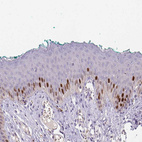

Immunohistochemistry analysis in human testis and pancreas tissues using HPA063242 antibody. Corresponding HELLS RNA-seq data are presented for the same tissues.